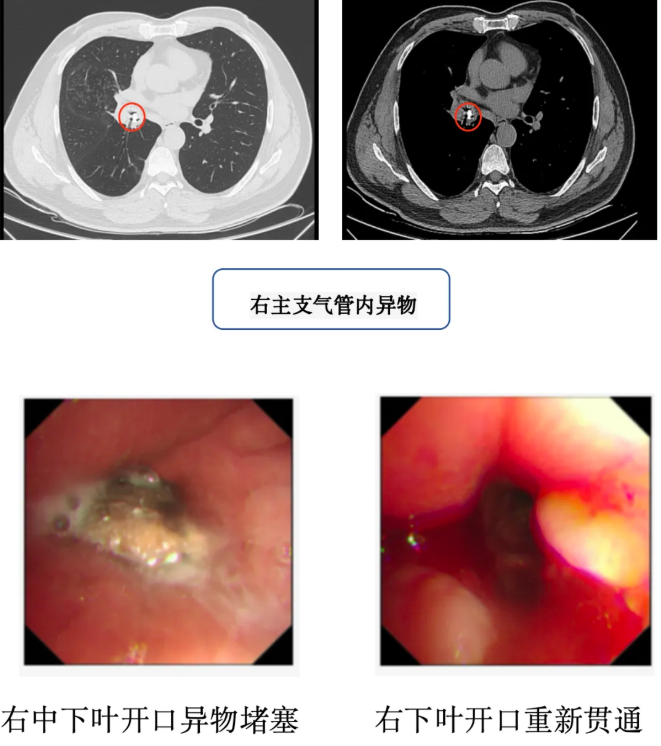

近日,广州中医药大学番禺医院(番禺区中医院)内五科成功为一名长期咳嗽的老年患者实施支气管镜手术,取出一块卡在右主支气管长达半年的鱼骨,彻底解除了患者的病痛。此案例再次提醒公众,尤其是老年人,进食时需格外警惕气道异物风险。

今年3月,周伯(化名)在吃鱼时不慎呛咳,此后出现间断性咳嗽、咳痰,症状持续半年未缓解。近期,他因症状加重至我院内五科就诊,经胸部CT检查发现,其右主支气管内有一异物存留,并已引发右中肺阻塞性肺炎。

较早前,内五科雷佩珊主任团队为周伯行支气管镜检查及异物钳取术。术中可见一块长约1.5厘米的鱼骨嵌顿于右中下叶支气管开口,周围黏膜严重水肿伴肉芽组织增生。

团队通过异物钳精准夹取鱼骨,并清理增生组织,手术历时20分钟,术后患者气道即刻恢复通畅,咳嗽、咳痰症状显著改善。